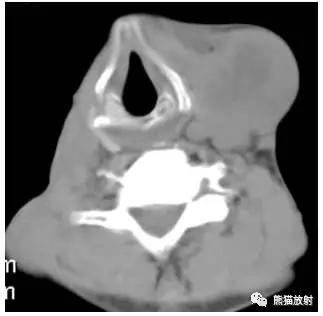

舌骨水平CT增强图像

横白线划在胸锁乳突肌后缘。

白线前为III区淋巴结,后为V区淋巴结。